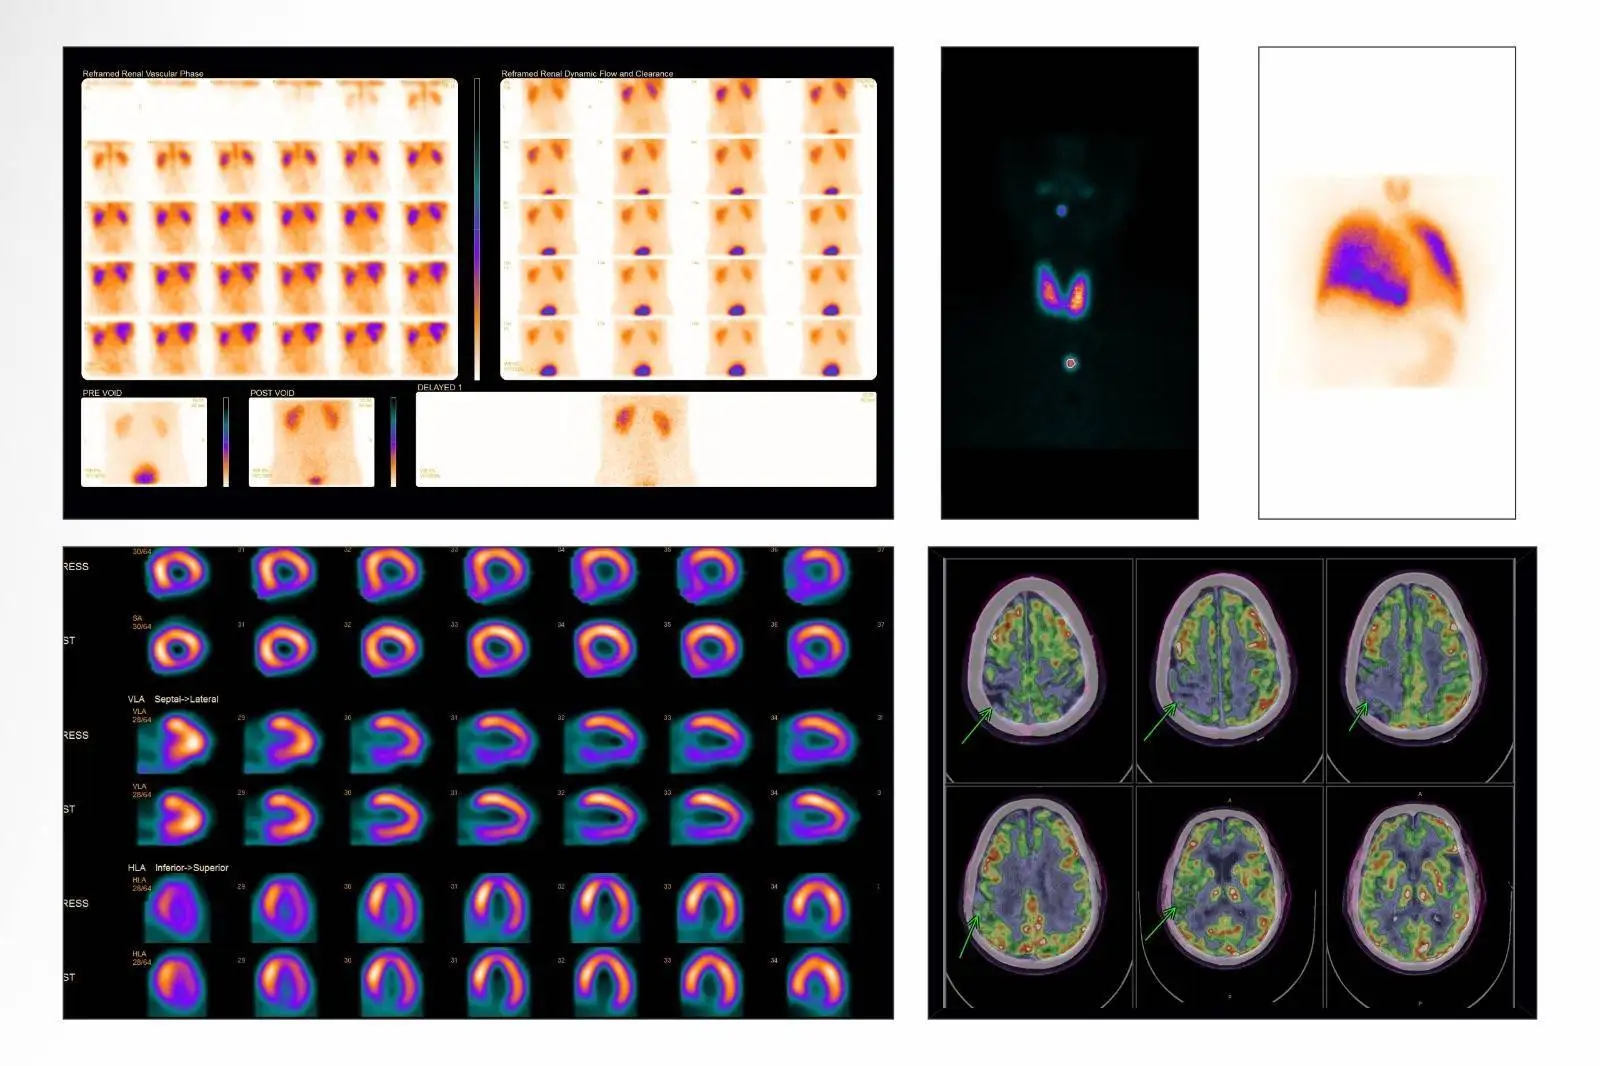

PET CT is a procedure where small amount of radioactive dye (radiopharmaceutical) is injected into patient to study the disease by combining the strengths of PET and CT imaging techniques

Patient is injected small amount of dye to study the specific organ and image is acquired on the gamma scan.

including PSMA PET/CT, DOTA PET/CT, and SPECT/CT for accurate staging, therapy planning, and follow-up.